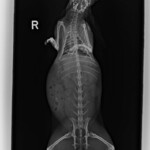

Pirátka Amálka již odcestovala do nového domova. Domov našla v Olomouci a i nadále bude pravidelně navštěvovat MVDr Agátu Sívkovou, která se o ní celou dobu skvěle starala. Amálce se pomoci dostalo opravdu na poslední chvíli. Její majitelé absolutně zanedbali péči o ní a pomoci se jí dostalo opravdu za 5 minut 12. První operaci podstoupila v psím azylu Zastavme utrpení z.s. a nadále jsme Amálku přijali pod svá ochranná křídla my. Díky vážnosti jejího stavu byla Amálka po celou dobu léčby v dočasné péči veterinářky, která dohlížela na její zdravotní stav. Podstoupila CT vyšetření a několik složitých operací (včetně sekání jařmové kosti) a i přesto, že její šance na přežití byly 50 na 50 jsme velice rádi, že jsme to nevzdali. Amálka je již v rámci možností v pořádku. Její zdravotní handicap ani komplikovanější povaha neodradila vážnou zájemkyni a králičce se tak naskytla skvělá příležitost nového domova v Olomouci kde jí budou dělat společnost dva králičí kamarádi Fousek a Albert. My bychom tímto chtěli poděkovat MVDr Sívkové za skvělou péči, MVDr Jeklovi a Hauptmanovi za provedení CT vyšetření a operací a samozřejmě i vám – našim fanouškům, kteří nás podporují a bez kterých bychom nikdy nemohli pomáhat v takové míře v jaké pomáháme a králíčkům bychom tak nemohli poskytnout nadstandardní veterinární péči. Děkujeme, že jste v tom s námi!